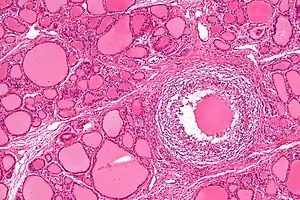

| Micrograph showing a granuloma in subacute thyroiditis. H&E stain. | |

Subacute thyroiditis is a form of thyroiditis that can be a cause of both thyrotoxicosis and hypothyroidism.[1] It is uncommon and can affect individuals of both sexes, occurring three times as often in women than in men.[2] and people of all ages. The most common form, subacute granulomatous, or de Quervain's, thyroiditis manifests as a sudden and painful enlargement of the thyroid gland accompanied with fever, malaise and muscle aches. Indirect evidence has implicated viral infection in the etiology of subacute thyroiditis. This evidence is limited to preceding upper respiratory tract infection, elevated viral antibody levels, and both seasonal and geographical clustering of cases. There may be a genetic predisposition. [3]